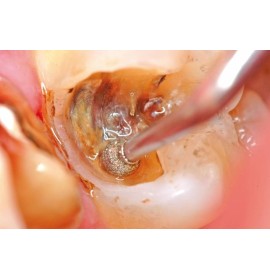

Система за интраорална диагностика.